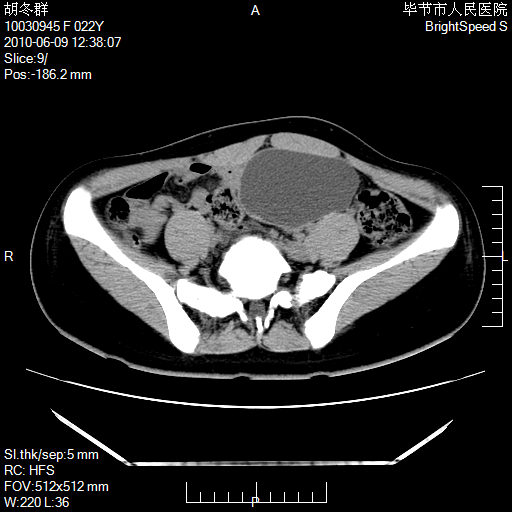

患者23岁,发现腹部包块3月。

盆腔内囊性占位;穿刺或者直接手术拿掉即可,不必紧张。

左侧卵巢囊腺瘤或囊腺癌

盆腔内囊性占位性病变;考虑左侧卵巢囊腺瘤。

有分隔、壁薄,支持考虑左侧卵巢囊腺瘤。

左侧卵巢浆液性囊腺瘤。

支持左侧附件区囊性占位,多考虑为囊腺瘤。